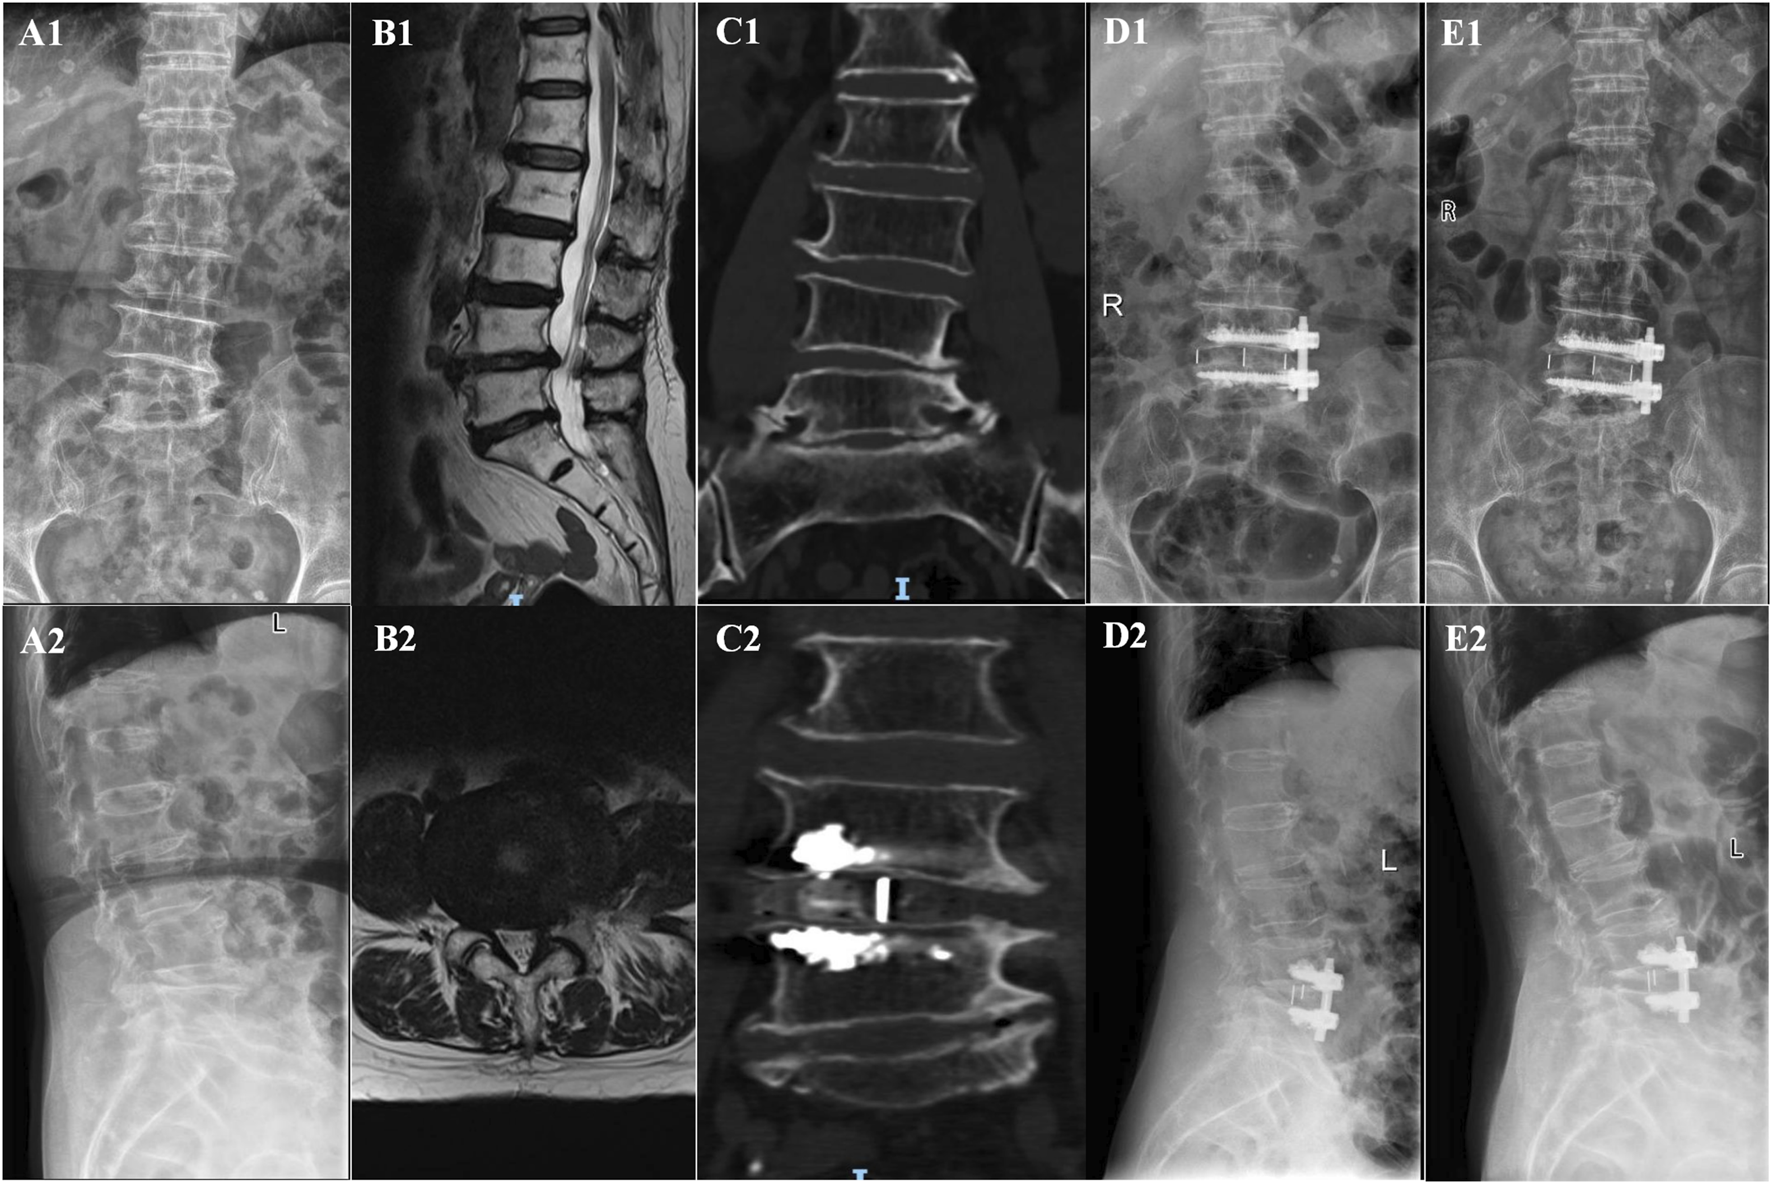

In the OLIF-BCAAS group, five cases (5/23, 21.74%) of CS were detected, with 4 out of 23 cases (17.39%) considered as mild CS. In contrast, the amount of CS was 12 cases (12/25, 48%) in the OLIF-PIFPS group, which included 3 cases of severe CS. There was a trend towards statistical difference in CS between the two groups (p = 0.057, Table 4). However, no significant differences were found in fusion rate at 6Â months and 12Â months postoperatively among the groups (p > 0.05, Table 4). Figures 2, 3 show the radiological images of the OLIF-BCAAS and OLIF-PIFPS typical cases.

FIGURE 2

The radiological images of OLIF-BCAAS typical case. (A1,A2) Preoperative A−P, lateral X-ray film; (B1,B2) Preoperative sagittal and axial MR images; (C1,C2) Preoperative and postoperative coronal CT; (D1,D2) A−P and lateral X-ray film at 1 day postoperatively; (E1,E2) A−P, lateral X-ray film at last follow-up postoperatively.